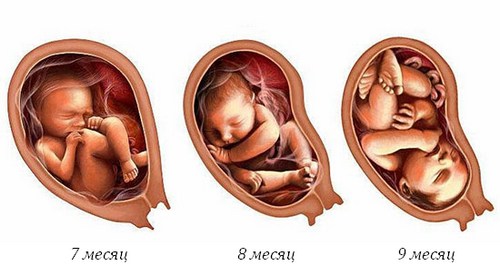

- зріст, вага плода збільшуються,

- ущільнюється шкіра, під нею утворюється жировий прошарок,

- інтенсивно розвиваються легені,

- збільшуються головний мозок, черепна коробка,

- навколоплідної рідини стає більше,

- плід займає певне положення в матці.

Для кожного скринінгу є свої терміни проведення: третій призначається в III триместрі, в період з 30 по 34 тижні вагітності (це норма). Конкретніше, коли робити УЗД і здавати аналіз крові, скаже лікар.

Чому саме цей проміжок часу використовується для досліджень внутрішньоутробного розвитку дитини? На це є свої причини: